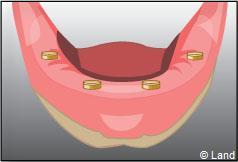

Les implants peuvent aussi servir à stabiliser un appareil amovible au maxillaire supérieur comme au maxillaire inférieur. Dans ce cas, les implants retiennent la prothèse amovible par des systèmes d’attachement.

Deux techniques sont possibles. Elles font appel à la barre de rétention ou aux boutons-pressions.